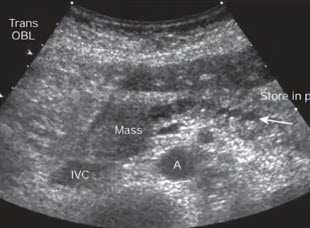

- Поперечное сканирование в эпигастральной области. Образование в головке (Mass), приводящее обструкции панкреатического протока. Четкообразное неравномерное расширение протока (стрелка). А - аорта, IVC - нижняя полая вена